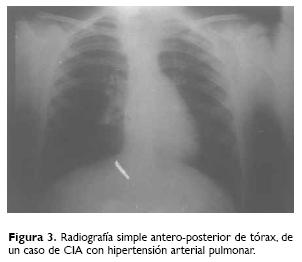

Los estudios de apoyo utilizados para el diagnóstico de SKF fueron radiografías de columna cérvicodorsolumbar, anteroposterior y lateral, otros con tomografía axial computada lineal y uno con resonancia magnética (Fig. 3).

De los 46 pacientes, 19 fueron valorados por el servicio de cardiología, de los cuales 12 correspondieron a corazón sano y siete con malformaciones cardiovasculares: uno con EP, el cual presentó gradiente transpulmonar de 40 mm Hg, uno con CIAostium secundum de 10 mm de diámetro con cortocircuito de izquierda a derecha asociada a insuficiencia pulmonar leve y vena cava superior izquierda, dos con dextrocardia (sin malformaciones cardiacas), dos con CIV perimembranosas pequeñas con HAP de 65 y 84 mm Hg respectivamente, y uno con HAP primaria, que cursó con 45 mm Hg de presión sistólica pulmonar; todos diagnosticados por ecocardiografía, excepto este último al cual se le realizó el diagnóstico con angiocardiografía (Cuadro 2). No fueron valorados por el servicio de cardiología en total 27 pacientes, por no presentar sospecha clínica de malformación cardiaca.